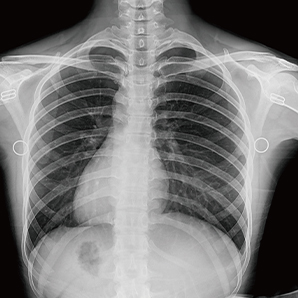

The high-performance imaging chain outputs reliable images as always. Subtle image details elevate diagnosis confidence to meet a broad range of clinical needs.